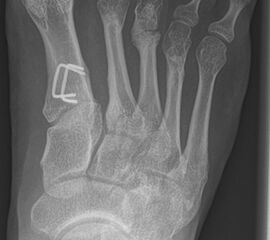

Wachstumslenkung mit moderner Klammer oder eight plate

Bei offenen Wachstumsfugen kann über eine Steuerung des Wachstums mit einer Klammer (Blount-Klammer/Flex Tack) oder kleinen Plättchen (Eight Plate) eine Korrektur von Achsabweichungen in der sagittalen und coronaren Ebene erreicht werden (Abb. 8). Der Hautschnitt beträgt ca. 1,5 - 2 cm und die so versorgten Kinder können ihre Extremität direkt postoperativ schmerzadaptiert voll belasten. Die wachstumslenkende Operation mit einer Klammer oder einem Plättchen besitzt ein enormes Korrekturpotential und erspart dem Kind oder Jugendlichen umfangreiche Umstellungsosteotomien und Plattenosteosynthesen, welche eine Schnittlänge von 15 cm und eine Entlastung des operierten Beines von 4-6 Wochen erforderlich machen.

Abb. 8 a-g: Genua vara prä- und postoperativ versorgt mit Flex Tacks (a-b) und ein Genu valgum versorgt mit Eight Plate an der medialen Femurkondyle (c); Spitzfuß bei congenitalem Klumpfuß und einem Flat Top Talus mit präoperativem Röntgenbild seitlich und der deutlich nach dorsal stehender Tibia(d); intraoperative Bilder der Epiphysiodese mittels Eight Plate zur Wachstumslenkung der distalen Tibia in die Extension (e-f) und postoperativer Verlauf nach sechs Monaten mit regelrecht stehender Tibia über dem Talus durch die distale Extension (g).

Zum Lesen der Bildbeschreibung und zur Vollansicht bitte die Bilder anklicken. Bilder: A. Helmers.